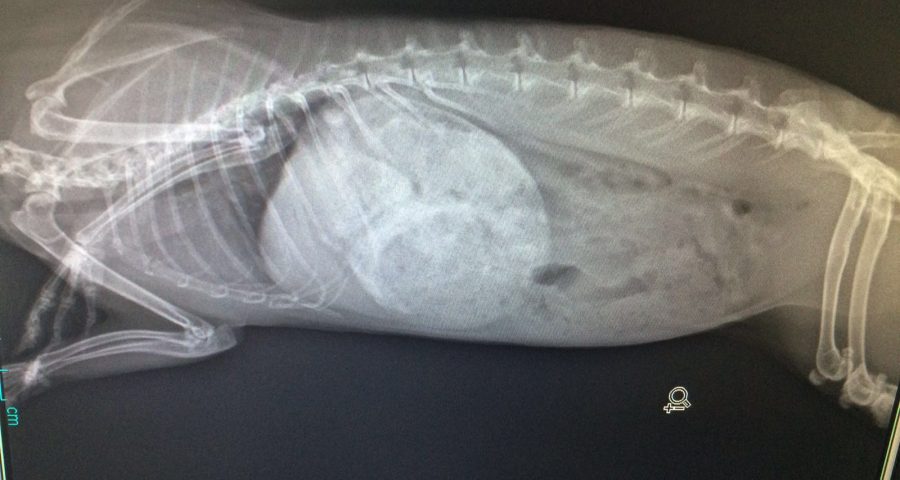

Ist das Kaninchen krank und trifft man beim Röntgen den richtigen Bereich, zeigen sich diverse sogenannte Röntgenzeichen, also sichtbare Abweichungen vom Normalzustand. Viele von ihnen sind so typisch, dass zusammen mit den Symptomen auf die Krankheit rückgeschlossen werden kann. Ist das Kaninchen z.B. sehr empfindlich im Bauchbereich und findet man dann einen aufgegasten Magen im Röntgenbild vor, ist die Krankheit schnell identifiziert und dem Kaninchen kann geholfen werden.

Der Bauchraum wird bei allen möglichen Verdauungsproblemen geröntgt, da z.B. das Ausmaß von Aufgasungen allein durch Abtasten oft nicht zuverlässig eingeschätzt werden kann. Besonders wichtig ist ein Röntgenbild hier, um sicher eine Aufgasung von einer Magenüberladung unterscheiden zu können – denn je nachdem, was vorliegt, ist die folgende Vorgehensweise sehr unterschiedlich und es ist lebenswichtig, dass hier richtig unterschieden wird. Auch muss bei Tumoren im Bauchraum röntgenologisch ausgeschlossen werden, dass Metastasten vorliegen. Bei Verdacht auf eine Blasenentzündung sollte ebenfalls ein Röntgenbild angefertigt werden, um auszuschließen, dass sich Ablagerungen in der Blase befinden, die dem Kaninchen Schmerzen verursachen. Auch eventuelle Vergrößerungen der Gebärmutter werden über ein Röntgenbild festgestellt.